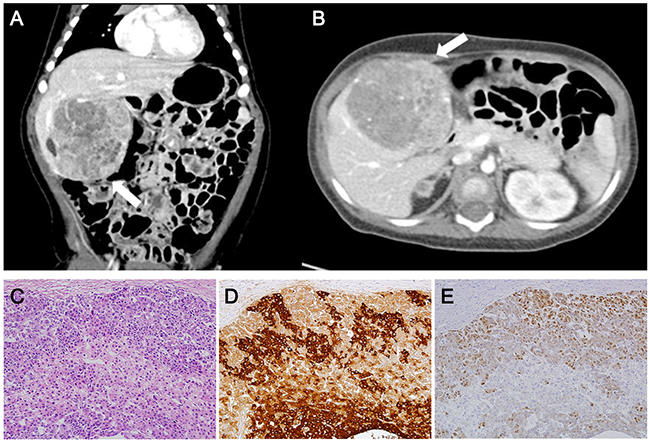

The baby was discharged at 1 month of age with a 3-month tumor screening schedule by abdominal ultrasonography and serum alpha-fetoprotein (AFP) as described elsewhere [12]. On his first visit to the outside clinic (+1 week after discharge), the AFP level was 6,428 ng/ml, which was decreasing compared to the initial AFP level of 124,704 ng/ml (Supplementary Figure 1). On the second visit (+9 weeks), it appeared that the AFP level was in the course of the natural decline and abdominal ultrasonography showed no evidence of hepatic tumor mass. On the third visit (+17 weeks), the AFP level had slightly increased, but abdominal ultrasonography was not performed due to the parent’s refusal. On the fourth visit (+29 weeks), his serum AFP level was elevated to >200,000 ng/ml and abdominal computer tomography scan revealed a well-defined heterogeneous liver mass (6.5 × 6.2 cm) (Figures 1A, 1B) suspicious of a hepatoblastoma. The hepatoblastoma was classified as PRETEXT stage II, a staging system for primary malignant liver tumors of childhood, that involved two sections (left medial and right anterior sections) of the four without any evidence of distant metastasis. He received transarterial chemoembolization with adriamycin and carboplatin, and neoadjuvant chemotherapy with cisplatin, vincristine and 5-fluorouracil. After 3 cycles of chemotherapy, hepatic segmentectomy (segment I, IV) was performed for curative surgery. The histopathologic diagnosis was hepatoblastoma with epithelial type (Figure 1C, 1D). He is now at complete remission state at 3 years post-operatively with five subsequent cycles of chemotherapy performed.

Figure 1: Abdominal computer tomography and histopathology of the case. Abdominal computer tomography scan at 8 months (coronary (A) and axial (B) view) showing a huge and well-defined heterogeneous mass suspicious of hepatoblastoma classified as PRETEXT stage II (arrow). Hematoxylin and Eosin staining (C), Immunohistochemistry for alpha fetoprotein (D) and β-catenin (E) show compatible features of hepatoblastoma.

Twelve non-silent gene mutations were detected: CTNNB1, OVGP1, SCN2A, HCLS1, MUC4, MUC6 OR10S1, TNRC6A, SLC9A5, SUGP2, ZNF99, and ZNF606 (Supplementary Table 1). Of them, only CTNNB1 was catalogued in the COSMIC cancer Gene Census, suggesting that the CTNNB1 mutation might be a driver. CTNNB1 c.G101T (p.G34V) somatic mutation was further confirmed with Sanger sequencing (Figure 4A). The CTNNB1 p.G34V has been reported as a recurrent driver mutation occurring in hepatoblastoma [14] and in other human cancers [15]. Immunohistochemistry revealed β-catenin nuclear staining in hepatoblastoma cells, suggesting activated Wnt signaling in the tumor (Figure 1E). Functional annotation of the mutated genes using the DAVID database [16] revealed that the Wnt signaling pathway was the most associated biological process (Supplementary Table 2), indicating that the activation of the Wnt pathway may be the key driver in sporadic hepatoblastoma [9-11] and in BWS-related hepatoblastoma.